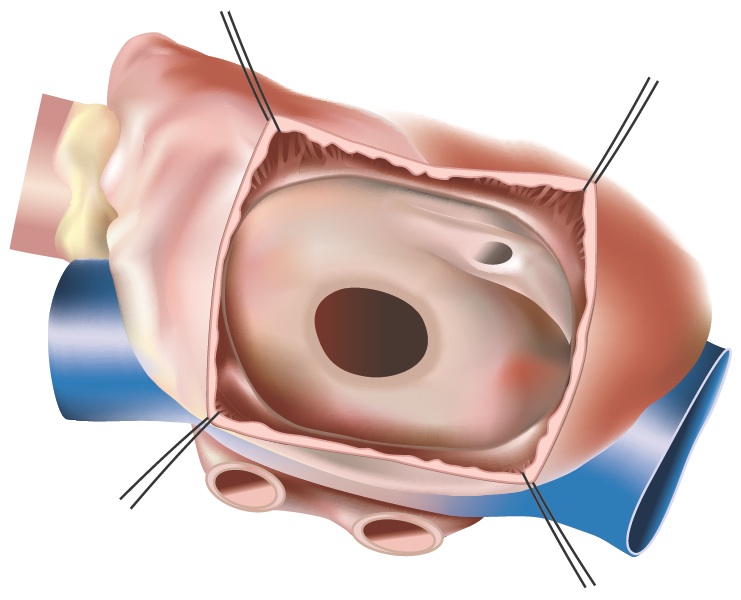

Patients are supported by a heart-lung machine intraoperatively and the ASD is approached through an opening in the right atrium

Figure 1 - Open ASD

Smaller ASDs can simply be closed using a suture and oversewing the hole. For larger ASDs, a patch is usually used to close the hole. This patch can be taken from the pericardium (the sac that surrounds the heart) or from synthetic materials such as Dacron or Teflon.